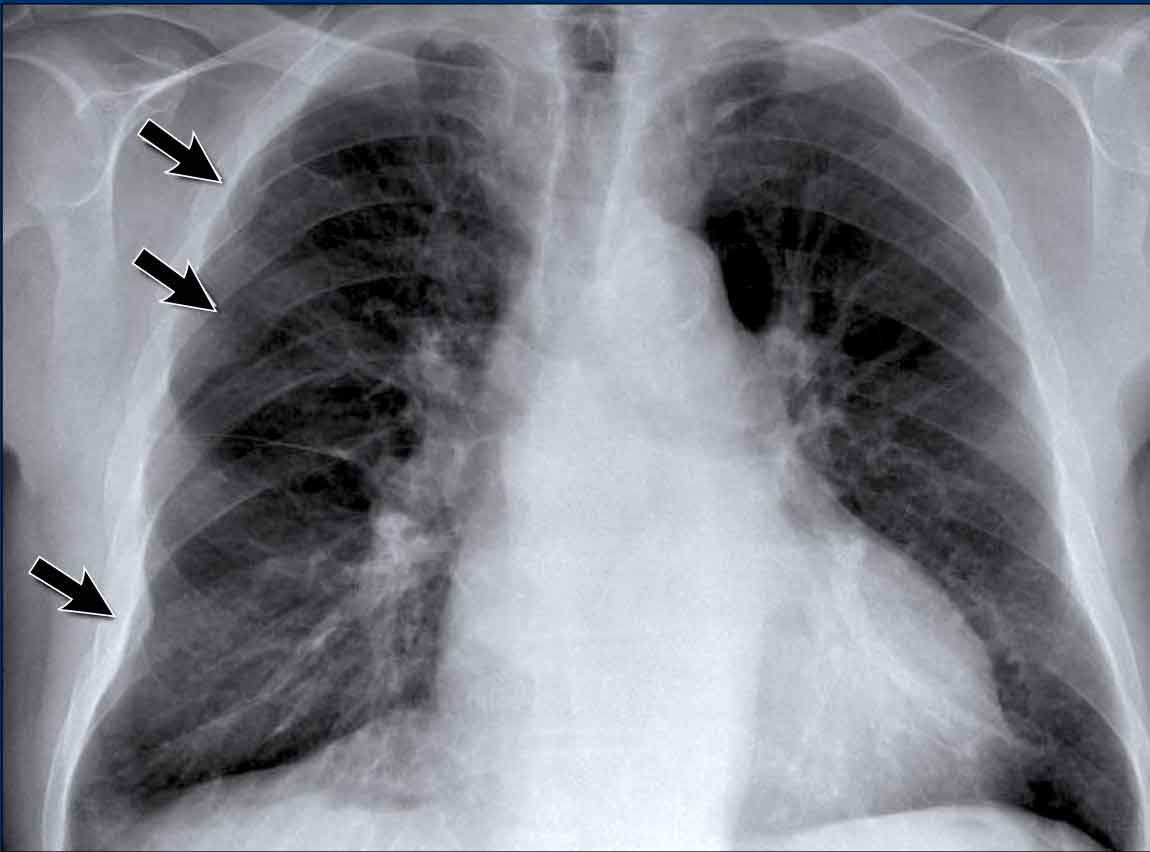

Pleural Plaques (Asbestos-Related)

• Multiple irregular pleural opacities are seen.

• Some follow the contours of the chest wall (arrows).

• Typical features of asbestos-related pleural plaques:

• Bilateral, extensive

• Often involve the diaphragmatic domes

Unilateral calcified pleural opacities may indicate: